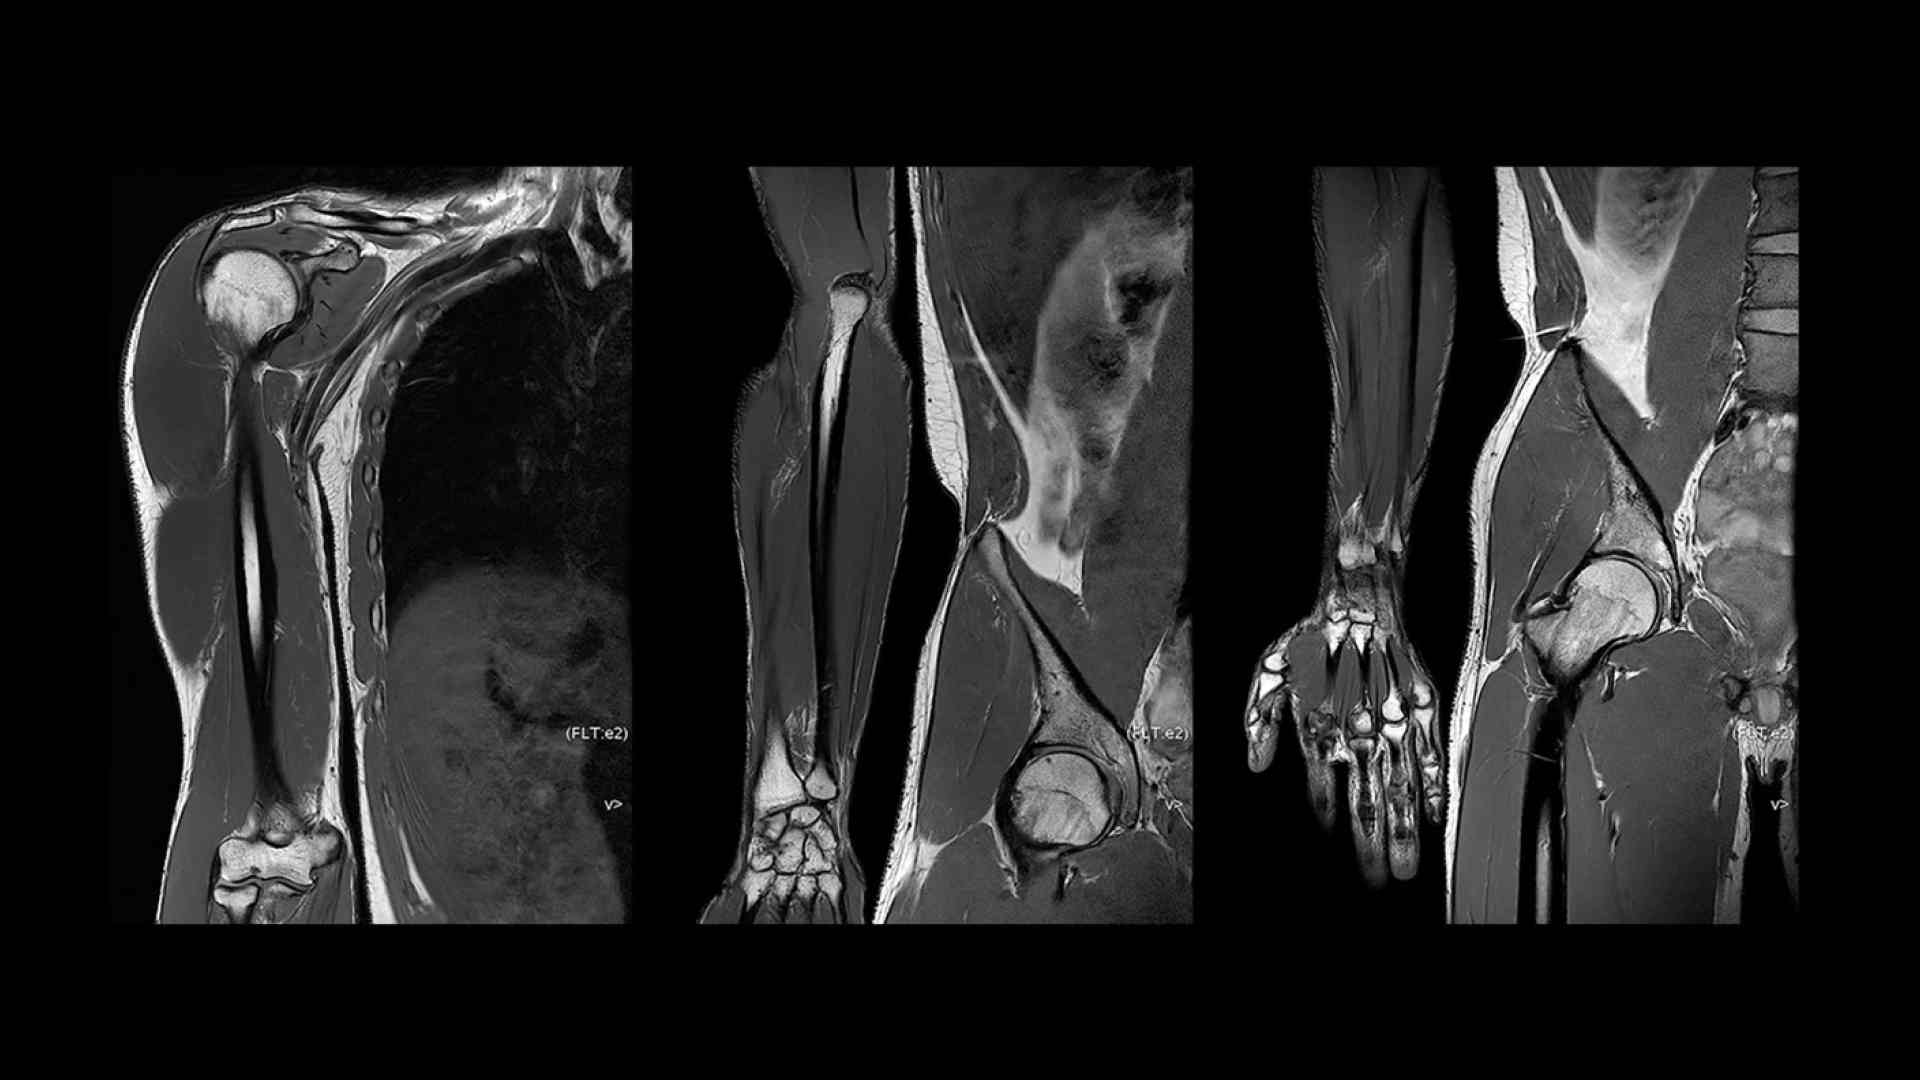

Pin-sharp image quality and exceptional speed with AIR™ Recon DL and Sonic™ DL​

SIGNA™ Premier offers the versatility you need to fulfill all your clinical needs. Explore the advanced imaging and clinical capabilities achievable with the SIGNA™ Premier system.

Experience pin-sharp precision and remarkable speed with a 3T SIGNA™ Premier MRI scanner, coupled with AIR™ Recon DL and Sonic™ DL.